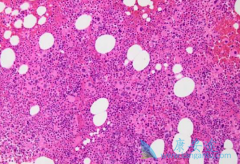

ENESTchina是一项随机、多中心试验,纳入267例新诊断(≤6个月)的c-CP成人患者,随机给予尼洛替尼( 达希纳 )300mgBID(n=134)或伊马替尼400mgQD(n=133),并根据Sokal评分和既往是否接受干扰素治疗对患者进行分层。结果显示,与伊马替尼组相比,尼 ...